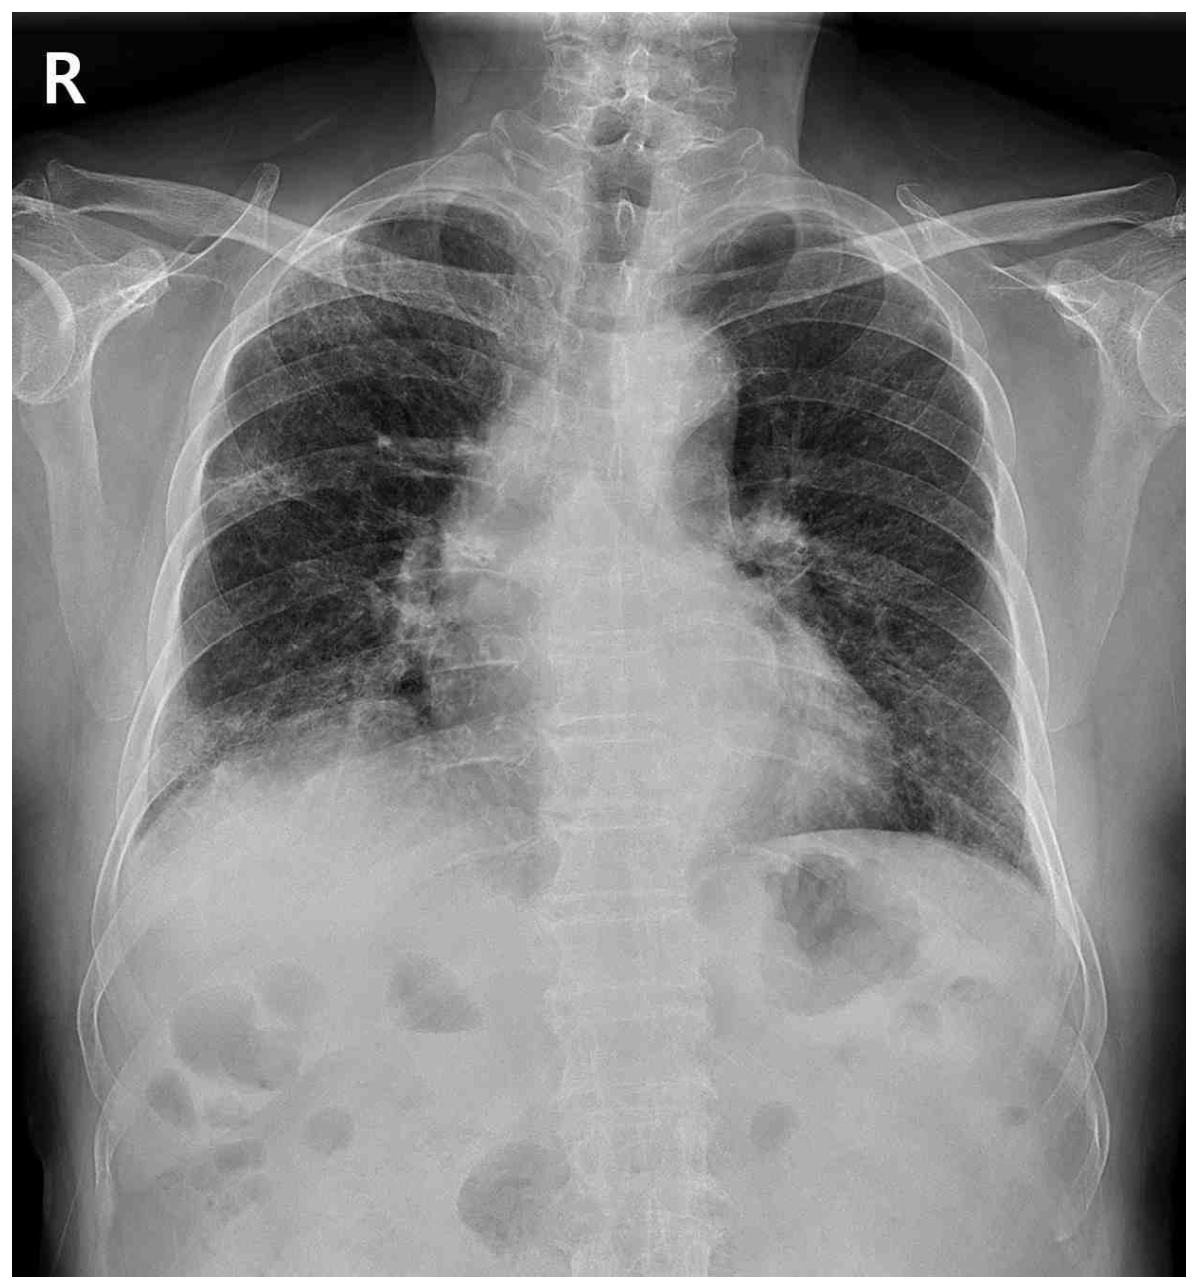

CXR: Bilateral reticular opacity

CXR상 양측 폐야에 증가된 opacity가 관찰되며, 더 자세한 평가를 위해 실시한 chest CT상 basal-predominant reticulation, mild honeycombing 및 GGO가 관찰되므로 간질성 폐질환(ILD)이 강하게 의심된다.